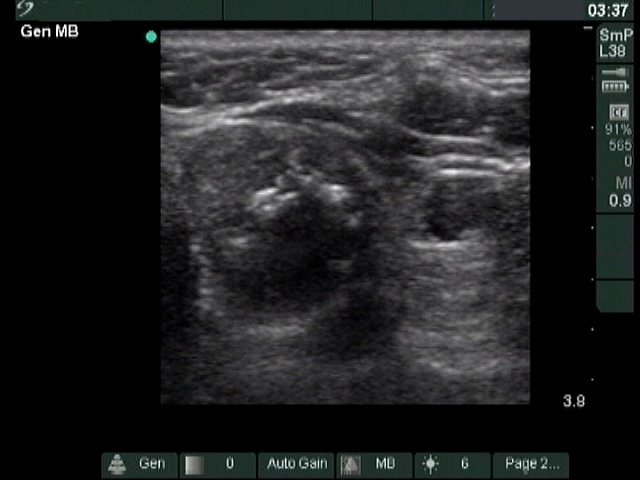

The composition of the nodule - case 1033 (ultrasonographic picture 5)

Middle part of the left lobe, transverse scan.